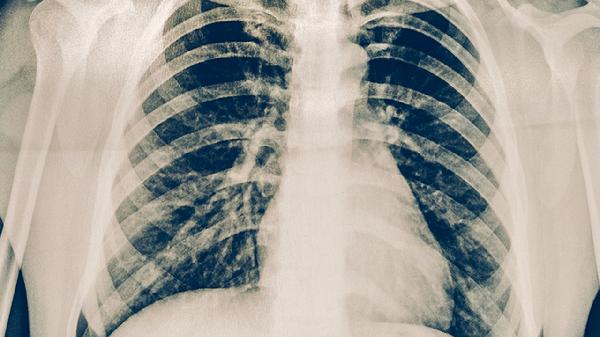

3. 临床表现评估

规范抗结核治疗2-3个月后仍持续发热、咳嗽、咯血或影像学进展,提示可能存在耐药。患者可能出现体重持续下降、夜间盗汗加重等全身症状。需注意这些表现缺乏特异性,需与治疗依从性差、合并糖尿病等非耐药因素鉴别。